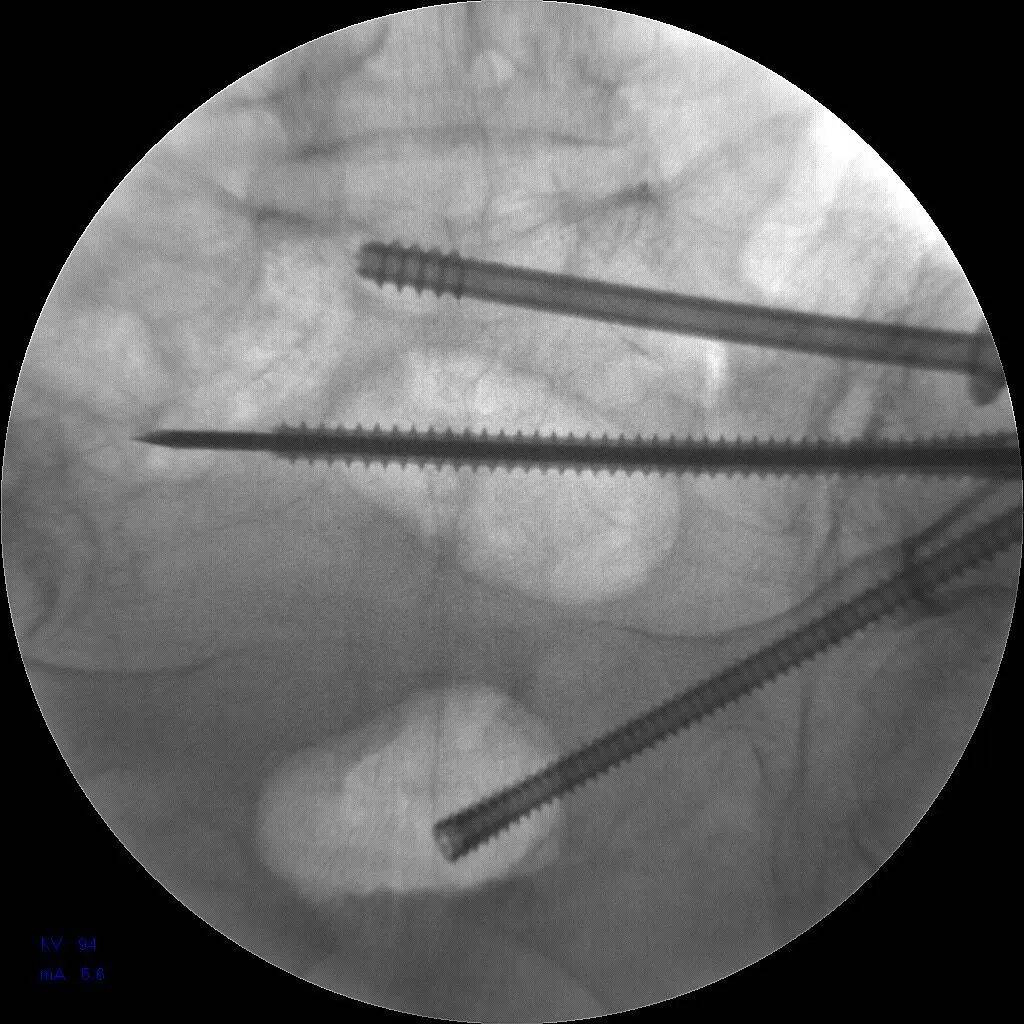

经过充分的术前准备,急诊科团队决定为姬奶奶实施骨盆骨折通道螺钉内固定术。与传统手术相比,它具有创伤小、恢复快、并发症少等诸多优势。手术室内,气氛紧张而严肃。医生们全神贯注,凭借着精湛的技术和丰富的经验,精准地将螺钉植入姬奶奶的骨盆骨折部位,固定骨折断端。每一个动作都小心翼翼,每一个步骤都精准无误,整个手术过程如行云流水般顺畅。